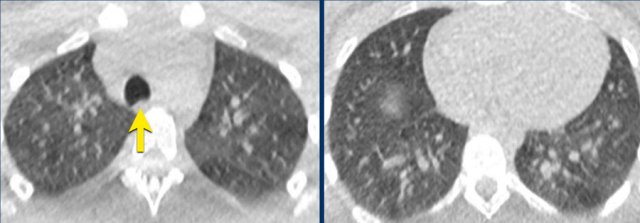

Alveolar hemorrhage

Bilateral and confluent airspace opacities caused by diffuse alveolar hemorrhage such as in e.g. systemic lupus erythomathosus on this image are distributed more along the bronchovascular bundles, and predominantly spare the peripheral pleural surfaces and costophrenic angles.

These opacities should resolve in weeks if bleeding does not recur.

The image shows alveloar hemorrhage with patchy groundglass along the bronchovascular bundles in a patient with secondary vasculitis in systemic lupus erythemathosus.

In COVID-19 the groundglass is more peripheral and diffuse.

More chronic or subacute hemorrhage causes crazy paving and fibrosis.

In addition, clinical presentation including fever, cough and leukocytosis are less common in patients with alveolar hemorrhage, although the clinical presentation of diffuse pulmonary hemorrhage remains highly variable.

Only approximately 2/3 of patients have hemoptysis